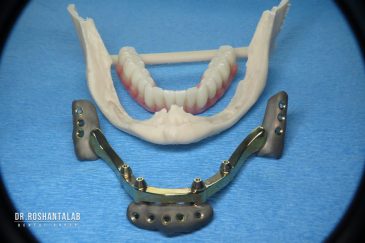

🔸 ایمپلنت دیجیتال و ساخت روکش دیجیتال

تجربه کاشت دندان دیجیتال و بدون درد در ۳ دقیقه! استفاده از برترین برندها زیر نظر جراح، با هزینه مناسب و خدمات کامل از کاشت دندان تا روکشارتودنسی دندان